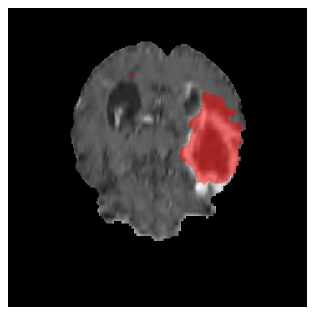

Appendix A Qualitative results

Figures 4 and 5 present the segmentation results for a patient from the BRATS dataset, visualized on a randomly selected slice. Figure 4 illustrates how tumor segmentation evolves over multiple episodes in S1 across different approaches including cumulative, naive, our approach, and the best buffer-free strategy (SI, =2). The cumulative approach, which trains on all encountered datasets together, maintains segmentation consistency across episodes but introduces significant amounts of false positives, particularly in the upper left area of the brain images. These misclassifications highlight its inability to generalize well across datasets despite access to all previous data. The naive approach, which learns sequentially without any continual learning strategy, suffers from severe catastrophic forgetting. While it initially segments well, performance deteriorates over episodes, leading to a near-complete loss of segmentation capability by the final episode. The SI (=2) approach, a regularization-based buffer-free CL strategy, performs reasonably well in early episodes but shows a significant performance decline over time. By the last episode, much of the tumor was no longer segmented, indicating difficulty in retaining prior knowledge. In contrast, our proposed approach initially produces more false positives but progressively refines its segmentation. By the final episode, it accurately retains the tumor region while minimizing misclassifications, demonstrating strong knowledge retention and adaptability across episodes. This suggests that our approach effectively mitigates catastrophic forgetting while maintaining segmentation performance over sequential learning.